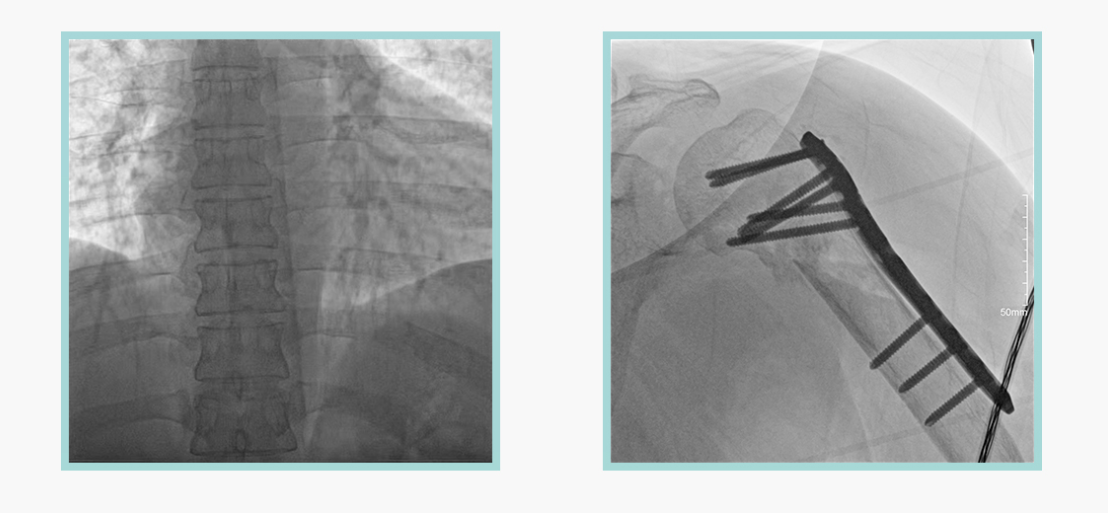

作為全球X線機的主要參與者,安健科技在數字化X線產品線實現全線動態化之外,在移動C臂X光機產品線領域推出全新平板移動C臂產品:悅畫。隨著國家“千縣工程”提升基層醫療衛生服務能力,外科對于手術介入引導設備的需求劇增。對于一臺優秀的移動C臂X線機而言,如何保證最優質影像的同時,最大程度降低X線的輻射劑量,并在滿足臨床手術引導/定位的同時,最大程度的保護臨床手術的醫務人員,是悅畫最為關切的問題。

安健科技悅畫移動C臂X線攝影系統,采用了業內技術最尖端的CMOS探測器。基于性能優異的針狀CSI閃爍體涂層和高靈敏度的CMOS感光芯片,悅畫可以實現在超低X線劑量條件下實現高清晰影像成像,相較于一般的影增移動C臂和平板C臂,動態范圍更高,影像的層次感和對比度更好。

在產品的性能參數設計上,悅畫的像素可達到200萬,空間分辨率可達到3.2線對,采用16bit的影像灰度,悅畫在影像后處理上,通過SPI金字塔圖像算法,支持攝影、脈沖透視影像、連續透視等多種模式下的影像采集,動態透視影像視頻支持保存與回放。雙大屏的設計,透視影像支持三檔放大,保證臨床影像讀取的便利。

此外,骨科手術時間平均時長約為45分鐘左右時間,長期的X線透視或攝影曝光劑量將對臨床手術與操作醫務工作者造成難以評估的健康風險,悅畫通過支持攝影曝光參數的自主調節,可以保證在最低劑量水平下輸出滿足臨床手術定位與引導所需要的影像質量,相較于市面上的固定曝光參數配置移動C臂,自主參數調節設計的曝光功能設計,可以大幅減少醫務工作者的X線輻射劑量。

悅畫在影像的偽影處理上,也積累多項圖像處理專利技術。通過對植入物的精準識別,悅畫能夠精準祛除植入物偽影與運動偽影,保證高質量的影像輸出,無論是影像的對比度、分辨率(清晰度)相較于市面上的移動C臂產品都更勝一籌。